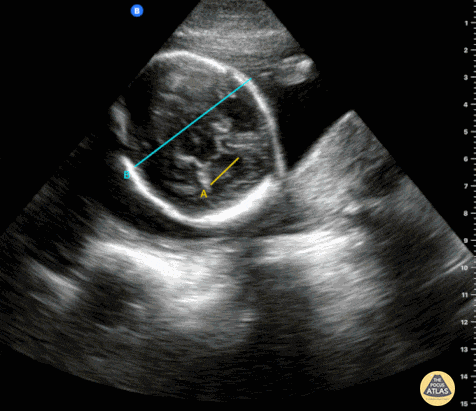

OB Dating Atlas - Week 22 - Biparietal Diameter (BPD)

An 18-year-old G1P0 with an LMP of “a few months ago” and no prior prenatal care presents to initiate care. She had a positive home UPT two months ago. On abdominal ultrasound, there is positive cardiac activity and positive fetal movement. The biparietal diameter measures 5.4 cm consistent with a 22w0d IUP. General Rules: Used to estimate gestational age starting at 14w0d Both measurements should be taken in the transverse plane at the level of the of thalami and cavum septum pellucidum with no cerebellum in view BPD: measure from the outer edge (closest to the probe) of parietal bone to inner edge on the opposite side (farthest away from u/s probe) Accuracy3: ± 7 - 12 d